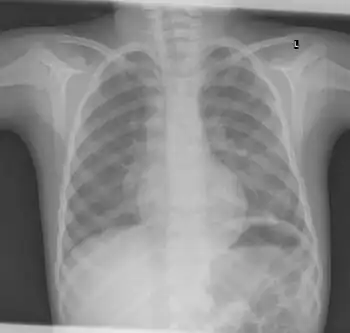

X-ray ribs: multiple enchondroma -

Enchondromatosis is the presence of multiple enchondromas, occurring as part of Ollier disease, Maffucci syndrome, or metachondromatosis.[3] It has a tendency to affect short tubular bones of the hands and feet, but can occur in long bones, shoulder blades and hips.[3] It presents with bone deformity, lumps, or broken bone, typically in a child.[2]